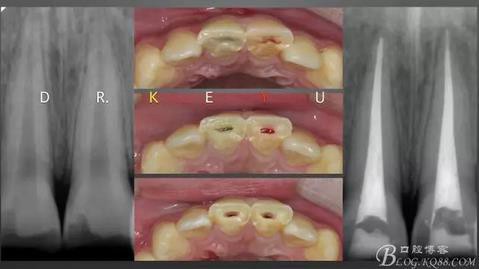

CASE 1—冠折后自體牙粘接,期待遠(yuǎn)期效果

360截圖20170120135019582.jpg

CASE 2—最初是樹脂關(guān)閉縫隙的病例,后來(lái)...

360截圖20170120135029229.jpg

后來(lái)因外傷冠折及時(shí)復(fù)診,11近中切角及樹脂一起折斷,21牙體完整(讓我相信了粘接的強(qiáng)大),再次樹脂修復(fù)(如果是瓷,我想就麻煩了)